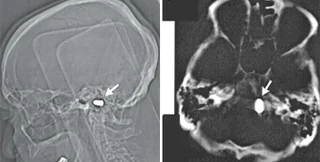

Тем не менее, сотрудники кардиоцентра доктор наук Марат Ежов, научный сотрудник отдела проблем атеросклероза Института клинической кардиологии РКНПК и ординатор этого отдела Майя Сафарова решили перестраховаться и назначили мужчине компьютерную томографию головы. Исследование показало, что у него в области большого отверстия затылочной кости находится пуля. При этом инородное тело не давило на жизненно важные органы и не вызывало опасных изменений в окружающих тканях.